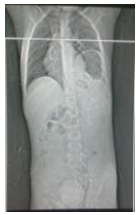

RN em sala de parto apresentou desconforto respiratório e foi encaminhado para UTI neonatal. Na admissão apresentava desconforto respiratório, cianose discreta e SO2 90%. Fez RX de tórax com o seguinte achado radiológico: Enunciado 4449891-1

Diante deste achado, assinale a alternativa que indica o diagnóstico e a melhor conduta.